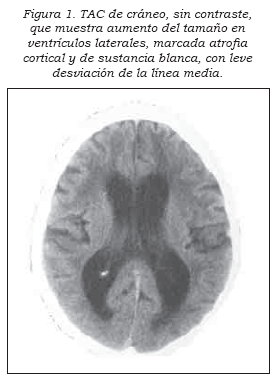

Un tomografía computada de cráneo mostró hidrocefalia global con atrofi a del cuerpo calloso (Figura 1). Después de una punción lumbar, realizada con fi nes diagnósticos, el paciente presentó desaparición del síndrome de Pisa, al igual que mejoría en la deglución y en los trastornos del sueño. Tuvo una presión (110 mmHg) y citoquímico normales, se suspendió la olanzapina y se recomendó iniciar neurorrehabilitación (5).

Las alteraciones en estos circuitos corticales-subcorticales explicarían los signos y los síntomas extrapiramidales, cognitivos y visuoespaciales que presentó este paciente, quien cumplió con los criterios de Relkin y cols. (11), entre estos el aumento del índice de Evans que, en nuestro caso, fue de 0,36 (normal <0,30).

La hipotrofi a/atrofi a o desplazamiento del cuerpo calloso da cuenta de las alteraciones de comunicación interhemisférica, que mejoran posderivación de LCR (17). El aumento de tamaño ventricular genera un efecto de masa intracerebral que comprime las estructuras subcorticales, demostradas en este caso por las alteraciones trigeminofaciales y somatosensoriales descritas arriba y evidentes en la tomografía craneana. Y aunque se considera que esta patología aparece en mayores de 40 años, ya hay indicios de que se presenta desde la niñez (18). Nuestro caso, muy probablemente, es el paciente más joven descrito hasta la fecha en Colombia.